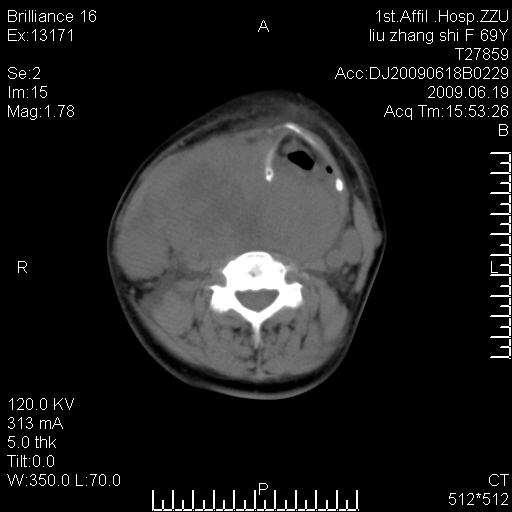

标题: CT26782:女,69岁,颈部占位,3天后公布病理结果。

【病理证实系列】女,69岁,颈部占位,有病理结果,3天后公布。(由于病例时间较久,临床资料不全,请网友见谅)本系列将有几百种常见、少见及罕见病例,均经病理证实。病例资料来自郑州大学第一附属医院。与网友共享,本人有空就发。

甲状腺癌并颈部淋巴结转移。感谢楼主的良苦用心,谢谢。

甲状腺癌并颈部淋巴结转移。

需与鼻咽癌鉴别!

支持甲状腺癌广泛侵及周围结构并颈部淋巴结转移。

鉴别:淋巴瘤、恶性神经源性病变、恶性纤维组织细胞瘤。

病理结果:颈部非霍奇金淋巴瘤。

右侧甲状腺确实有问题